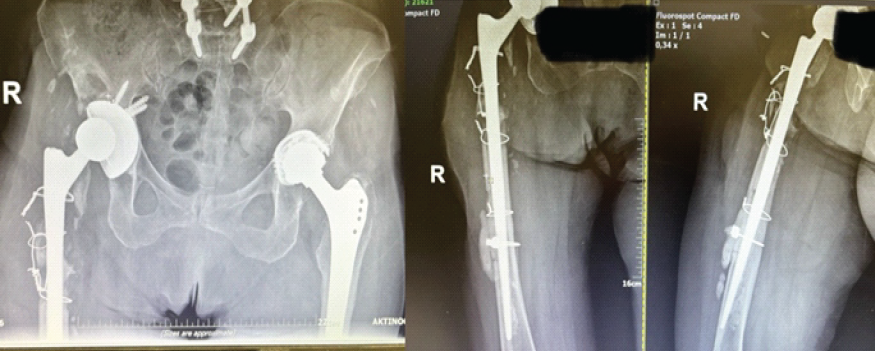

An 85-year-old female patient underwent a primary THA in 1999. In 2021, she required her first revision THA operation, due to mechanical loosening of the implant without any signs of infection after laboratory and clinical evaluation. Three weeks after the revision, the patient sustained a prosthetic hip dislocation, which was treated with open reduction. Due to persistent instability, a second revision THA was performed 3 weeks later. All of the aforementioned interventions were performed at another institution. Four weeks after this latest revision, the patient presented to our outpatient department with a draining sinus located near the surgical incision of the right hip. Following multidisciplinary team discussion, she was admitted to our hospital for further evaluation (Fig. 1).

Figure 1: Revision total hip arthroplasty with a sinus tract infection upon presentation.